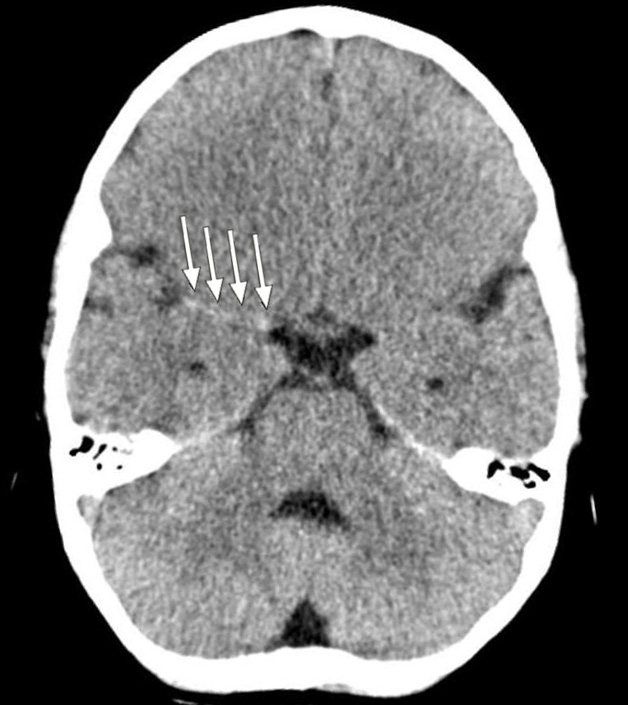

Et barn ble innlagt med en nyoppstått venstresidig hemiparese. CT caput ved innkomst viste «tett media-tegn» (dense media sign) (piler), noe som ga mistanke om en langstrakt trombe i høyre a. cerebri media (bildet til venstre). Pasienten fikk gradvis fallende bevissthetsnivå, og det ble gjort MR-undersøkelse. Denne viste nedsatt diffusjon som tegn på ferskt infarkt i hele forsyningsområdet til a. cerebri media samt begynnende ødem (bildet til høyre).

Nevrokirurgisk avdeling ble kontaktet, og på vital indikasjon ble det utført en trykkavlastende hemikraniektomi. På tross av kirurgisk intervensjon og medikamentell behandling lyktes man ikke med å kontrollere det intrakraniale trykket, og pasienten døde tre dager senere.

Malignt hjerneinfarkt defineres som et infarkt med påfølgende romoppfyllende, livstruende ødem. Mortaliteten kan være så høy som 80 % med konservativ behandling (1). Det foreligger tre randomiserte, kontrollerte studier som har vist at trykkavlastende hemikraniektomi innen 48 timer gir redusert mortalitet og bedrer utfallet hos voksne under 60 år (1). Trykkavlastende hemikraniektomi ved malignt hjerneinfarkt hos barn er en svært sjelden prosedyre, men studier har vist at tidlig intervensjon kan føre til et godt funksjonsnivå (2).